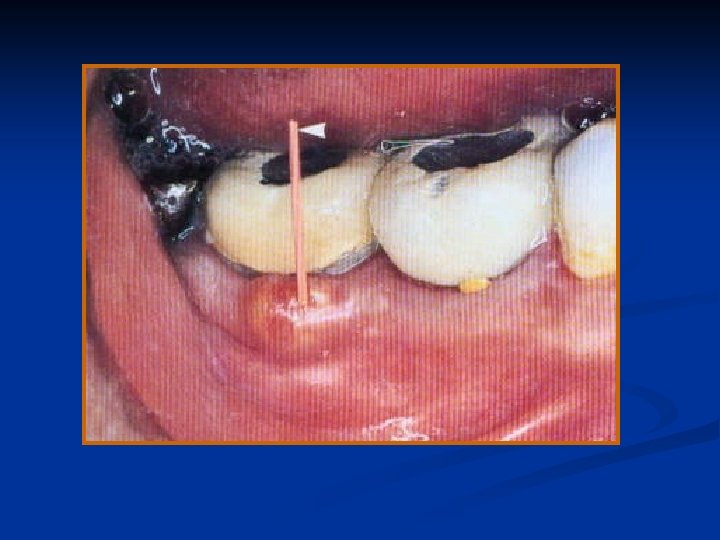

Symptoms: A tooth with chronic alveolar abscess is generally asymptomatic; at times, such an abscess is detected only during routine radiographic examination or because of the presence of a sinus tract.

Diagnosis: A chronic abscess may be painless or only mildly painful. At times, the first sign of osseous breakdown is radiographic evidence seen during routine examination or discoloration of the crown of the tooth.

When asked, the patient may remember a sudden, sharp pain that subsided and has not recurred, or he may relate a history of traumatic injury. The tooth does not react to the electric pulp test or to thermal tests.